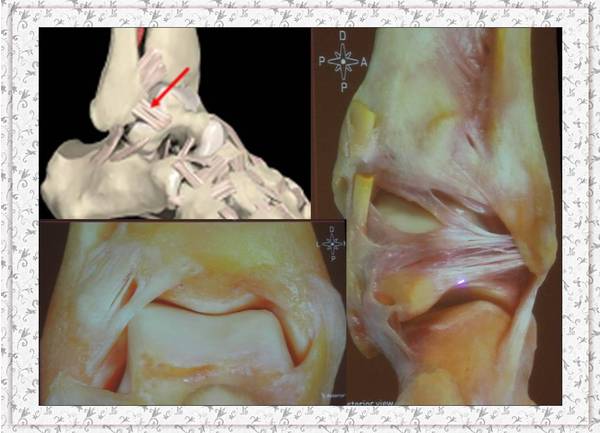

今天康复科李淑媛医生给我们讲了生动的一课。

题目是《慢性踝关节不稳的诊断与治疗》

上传部分课件大家共同分享、学习、进步。